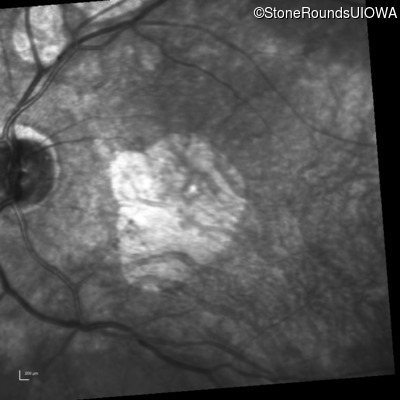

Best Disease (IIB)

Visit at age: 42 years

Infrared Fundus Photograph - Right - 20/125 -2

Best Disease BEST1 Tyr227Asn TAC>AAC   AD